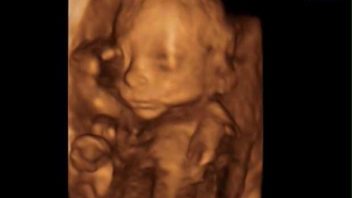

„Nesprchovala jste se náhodou?“ zeptala se mě sestřička, asi se snažící o vysvětlení, co to teda bylo za tekutinu. Tak pochopitelně jsem se osprchovala, že? Ale že bych se sprchovala stylem jupí sprcha do vagíny, to opravdu ne. Pak mi bylo řečeno, že to taky mohl být gel na vyšetřeni, co můj gynekolog ráno použil na ranní prohlídce. To už jsem se tedy cítila opravdu jako debil. Navíc ošetřující lékařka, která mě vyšetřila pohmatem a pak i ultrazvukem zjistila, že mám čípek dlouhý jak písničku a opravdu že nic nenasvědčuje tomu, že bych rodila. Jen, že hlavička dole hodně naléhá.

Vzala mi ovšem ještě dva stěry na další dva testy. Druhý byl negativní, ale ten třetí, ten už byl pozitivní. Na kebab jsem mohla zapomenout. Dostala jsem nemocniční košilku a vzhledem k tomu, že neměli místo na normálním pokoji, umístili mě na malém porodním sálku. Naordinovali mi kapák magnezia, které by mělo pomoci. Pro jistotu mi píchli ještě kortikoidy na dozrání plic maličké, kdyby se porod náhodou rozjel. Davida poslali domů. Za to jsem moc ráda nebyla, nechtěla jsem hysterčit a oponovat doktorům, ale cítila jsem, že pravděpodobně začínám rodit. Jistá jsem si však nebyla. Jako prvorodička jsem důvěřovala lékařům.